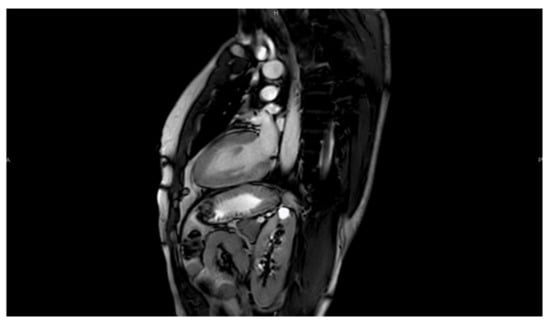

4. Cardiac Magnetic Resonance (CMR)

Cardiac magnetic resonance imaging (CMR) exploits the capacity of hydrogen protons that are abundant in the water and in the fat of biological tissues to absorb radiofrequency energy when placed in an external magnetic field. As a result, an evolving spin polarization can induce a signal in a radiofrequency coil, to be detected by antennas and after signal analysis to reconstruct high-resolution images. The most common CMR sequences are T1-weighted and T2-weighted scans in which we can measure very accurately left and right ventricular volumes, ventricular mass, atrial volumes, and vessel dimensions [15].

4.1. T1-T2–LGE

One of the main advantages of CMR over other imaging techniques relies on myocardial tissue characterization. T1-weighted sequences are very useful to visualize cardiac anatomy in great detail and detect the presence of intra-myocardial fat. T1 mapping can also quantify myocardial fibrosis [16]. For the detection of myocardial edema, the best modality is the use of T2-weighted imaging. Additionally, the use of contrast agents such as gadolinium can significantly increase the diagnostic capacities of CMR (Figure 9 and Figure 10). Late gadolinium enhancement (LGE) is a useful tool for the proper identification of infarcted myocardium. This technique is mainly used along with perfusion CMR to assess whether a wall region in question is ischemic or infarcted (scar) [17,18].

Further functional and structural information can be acquired thanks to the development of a magnetic resonance sequence called balanced steady-state free precession (bSSFP) cine imaging. They are usually retrospectively gated and have intrinsically high contrast. Images are typically planned sequentially to achieve the standard cardiac planes to access left and right ventricular size and function and can be played in video mode which allows evaluation of biventricular volume, mass, and EF with valvular motion [16,17,18].

Figure 9. CMR image 4CH view of the heart.

Figure 10. CMR image 2CH view.